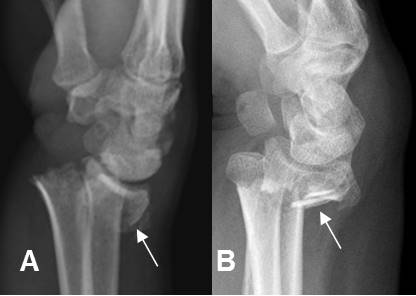

Fig 187. Fractura de Galeazzi.

A: Rx lateral, B: Rx AP y C: Rx oblicua. Fractura espiroidea y algo cabalgada, del radio y luxación en la articulación radioulnar distal.

Fig 199. Fractura de Monteggia.

A: Rx AP y B: Rx lateral. Fractura conminuta con angulación anterior del cúbito proximal (Flecha delgada) y luxación en la cabeza del radio. (Flecha gruesa).